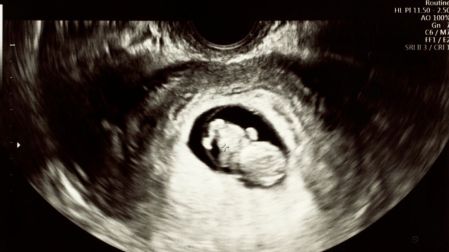

Históricamente, el sistema de salud considera que, si una mujer sobrevive al parto sin hemorragias inmediatas, el peligro ha pasado. Pero la investigación sugiere lo contrario, subraya que muchas de estas complicaciones (como la preeclampsia tardía o la miocardiopatía periparto) se manifiestan cuando la paciente ya está en casa, lejos de los monitores de alta precisión.

Aunque se asocia principalmente con el embarazo, la preeclampsia puede debutar hasta seis semanas después del nacimiento. Los picos de hipertensión arterial pueden causar daño orgánico severo antes de que se presenten síntomas evidentes como visión borrosa o dolor en el epigastrio. Según el estudio de CMAJ, la detección tardía de esta condición es uno de los factores que más influyen en las complicaciones graves.